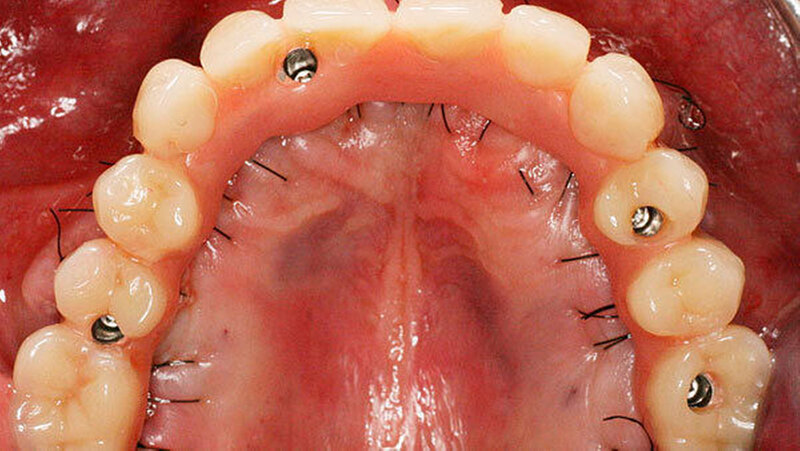

Eine erhebliche Erweiterung der Indikation des All-on-4 Konzeptes konnte durch den Einsatz von Zygoma-Implantaten erzielt werden. Zygoma-Implantate werden im Os zygomaticum verankert und erreichen auch in Situationen mit starker Kieferkammatrophie eine hohe Primärstabilität. Herkömmliche augmentative Verfahren können so vermieden werden. Zygoma-Implantate wurden zunächst bei Patienten mit besonderen Dysplasien im Kieferbereich und bei Tumorpatienten nach Resektion von Kieferanteilen eingesetzt. Balshi war einer der ersten Kliniker, der mit speziell gestalteten Implantaten entsprechende Fälle versorgte. Die Übertragung des All-on-4 Konzeptes auf Zygoma-Implantat-getragene Versorgungen ist insbesondere mit dem Namen Malavez verbunden, die sich sehr um diese Technik verdient gemacht hat. Dieses Konzept auf Zygoma-Implantaten wird angewendet in Fällen mit ausgeprägter Kieferkammatrophie im Oberkiefer (Abbildung 4a). Die Zygoma-Implantate werden in aller Regel in ITN inseriert. Lediglich ein externer Sinuslift ist als augmentative Maßnahme notwendig (Abbildungen 4b und c). Durch dieses Vorgehen können aufwändige augmentative Verfahren umgangen werden. Die prothetische Versorgung der Zygoma-Implantate entspricht dem Vorgehen wie beim All-on-4 Konzept und erfolgt einen Tag postoperativ. Erreicht wird, wie beim ursprünglichen All-on-4 Konzept, eine festsitzende Sofortversorgung (Abbildungen 3 und 4d).

Während die Behandlungszeit bei komplexen Augmentationen ein Jahr und mehr betragen kann, ist bei Verwendung von Zygoma-Implantaten eine festsitzende Sofortversorgung möglich. Eine Kombination von konventionellen Implantaten bei lokal ausreichendem Knochenangebot mit Zygoma-Implantaten bei lokal unzureichendem Knochenangebot ist möglich.